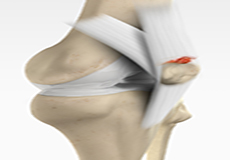

Anterior Cruciate Ligament (ACL) Tear

The anterior cruciate ligament, or ACL, is one of the major ligaments of the knee that is in the middle of the knee and runs from the femur (thighbone) to the tibia (shinbone). It prevents the tibia from sliding out in front of the femur. Together with posterior cruciate ligament (PCL) it provides rotational stability to the knee.